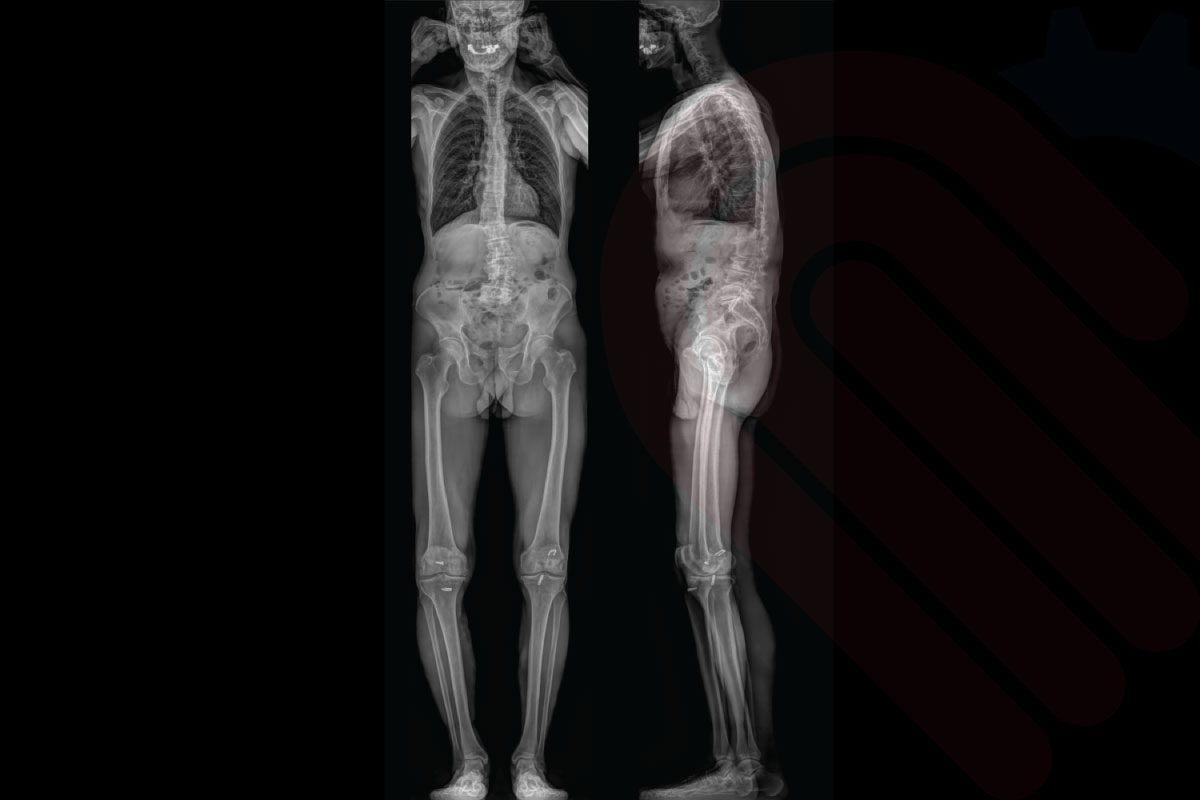

EOSedge®, ortopedi ve kas-iskelet sistemi tanısında yeni bir standart belirleyen, düşük doz radyasyonla yüksek çözünürlüklü biplanar görüntüleme sağlayan gelişmiş bir sistemdir. Skolyoz, kalça-diz deformiteleri, alt ekstremite hizalanma bozuklukları ve travma sonrası değerlendirmelerde; 1:1 oranlı, distorsiyonsuz ve yük taşıyan pozisyonda alınan görüntülerle cerrahlara güvenilir tanı ve cerrahi planlama imkânı sunar.

EOSedge, hastanın başından ayak bileğine kadar tek pozisyonda tam vücut görüntüleme imkânı sunar. Geniş görüş alanı ve dikey tarama teknolojisi sayesinde tüm iskelet yapısı doğal yük taşıma pozisyonunda görüntülenir. Bu, skolyoz, bacak uzunluğu farklılıkları ve eklem hizalanma bozukluklarının değerlendirilmesinde kritik öneme sahiptir.

EOSedge, aynı anda hem önden (AP) hem de yandan (lateral) yüksek çözünürlüklü görüntüler alabilen biplanar görüntüleme teknolojisine sahiptir. Bu sayede, hasta tek bir pozisyonda dururken iki farklı perspektiften tam iskelet görüntüsü elde edilir. Biplanar yapı, anatomik detayların doğru şekilde değerlendirilmesini sağlar ve cerrahi planlamalarda yüksek doğruluk sunar.